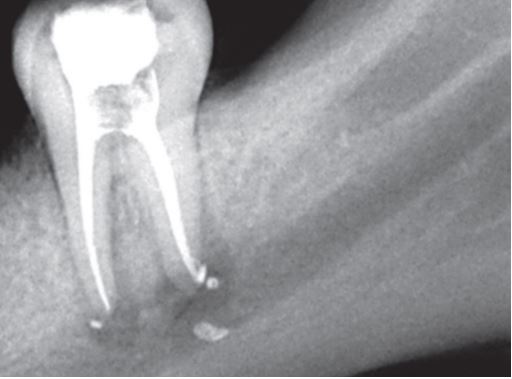

– Đưa dụng cụ quá chóp (H21.2).